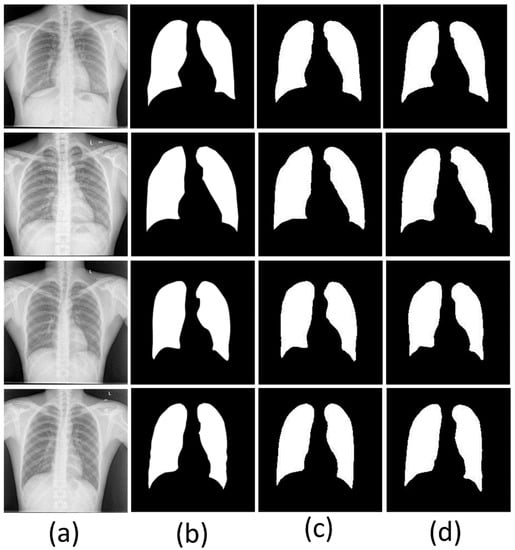

3.1. Segmentation

3.1.6. Segmentation of the Classification Dataset